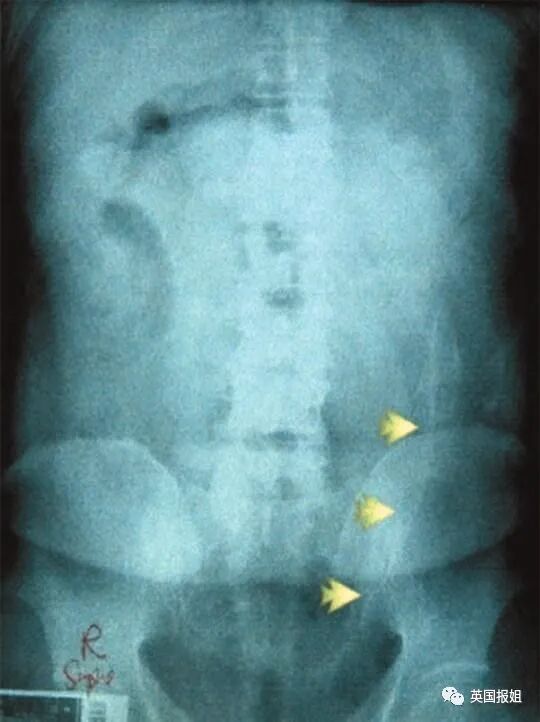

上个月,巴西某监狱一位男性囚犯肛门中被发现有8部带电的手机,4根USB线,7个手机芯片还有1根充电器电线…

他当时是刚到达监狱,接受电子检查,体内的电子装置直接被扫描仪显示出来了。

好家伙,这琳琅满目的电子产品,感觉在监狱里开个手机店都不成问题了。

他这也是靠“非法偷渡”挣钱,把这些手机、充电线都包好了塞进屁股,通过人体运送进监狱,分给需要的狱友,交易完成之后他就能得到一笔相应的钱。

最后这个男囚不需要医疗帮助,自己把8部手机、充电线啥的都排出来了。